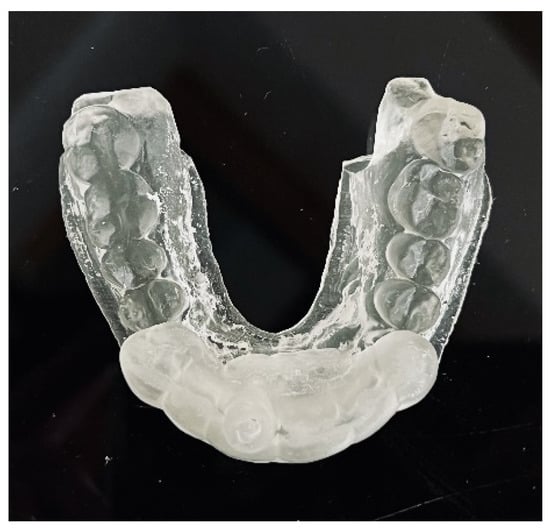

After the implant position was accepted by a clinician, an endodontic guide (teeth-supported) was designed for a sleeveless, static navigation of the image obtained from an intraoral scan (Figure 12). The guide covered the labial and palatal surfaces of the adjacent teeth (13-23) to obtain adequate intraoral stabilization. The use of stabilizing pins is unnecessary in such cases. The guide tube was designed so that the top of the sleeve was 21 mm from the radiographically visible root canal lumen. The guide sleeve was 6 mm long and 1.5 mm in diameter. The endodontic guide was printed on a resin 3D printer (Phrozen Sonic Mini 4K) using a transparent resin designed for printing surgical guides (NextDent SG)—a class IIa product that can be used in the oral cavity (Figure 13). Post-processing was conducted in accordance with the resin manufacturer’s instructions to avoid dimensional changes [24]. A master model was printed to check the accuracy of the guide’s fitting (Figure 14).

Figure 13. Three-dimensional printed endodontic guide.